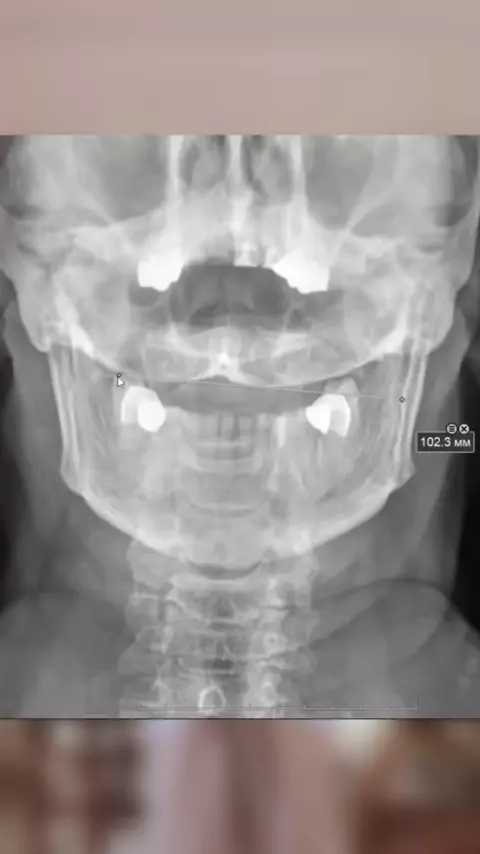

А вы уверенны в себе ?🫵🏻 #психосоматика#шея#неуверенность#шейныйотдел#энергия#достижениецелей#костоправ#биомеханика#перфекционизм#трудности#хиропрактика#психология